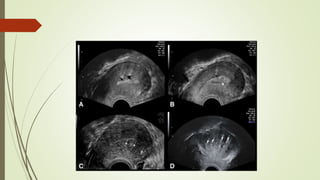

AUB-A

 Adenomyosis is the presence of ectopic endometrial glands and stroma located within the

myometrium of the uterine wall.

 diffuse or focal involvement of the myometrium.

 C/P pelvic pain, progressive dysmenorrhea, HMB, and tender symmetrically enlarged

uterus

 Investigation

1- U/S : diffusely symmetrically enlarged uterus with cystic areas found within the

myometrial wall (Myometrial cyst).

2- MRI Accurate diagnosis .Diffuse or focal widening of JZ(--Increase junctional zone >12 mm)

 Treatment : LNG-IUS , adenomyomectomy and Hysterectomy